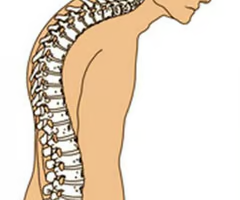

Cervical

Thoracic

Lumbar

Sacrum

Coccyx

Kyphosis

“Hunchback,” is an exaggerated thoracic curvature.

Lordosis

“Swayback,” is an accentuated lumbar curvature.

Scoliosis

Abnormal lateral curvature, usually in thoracic region.